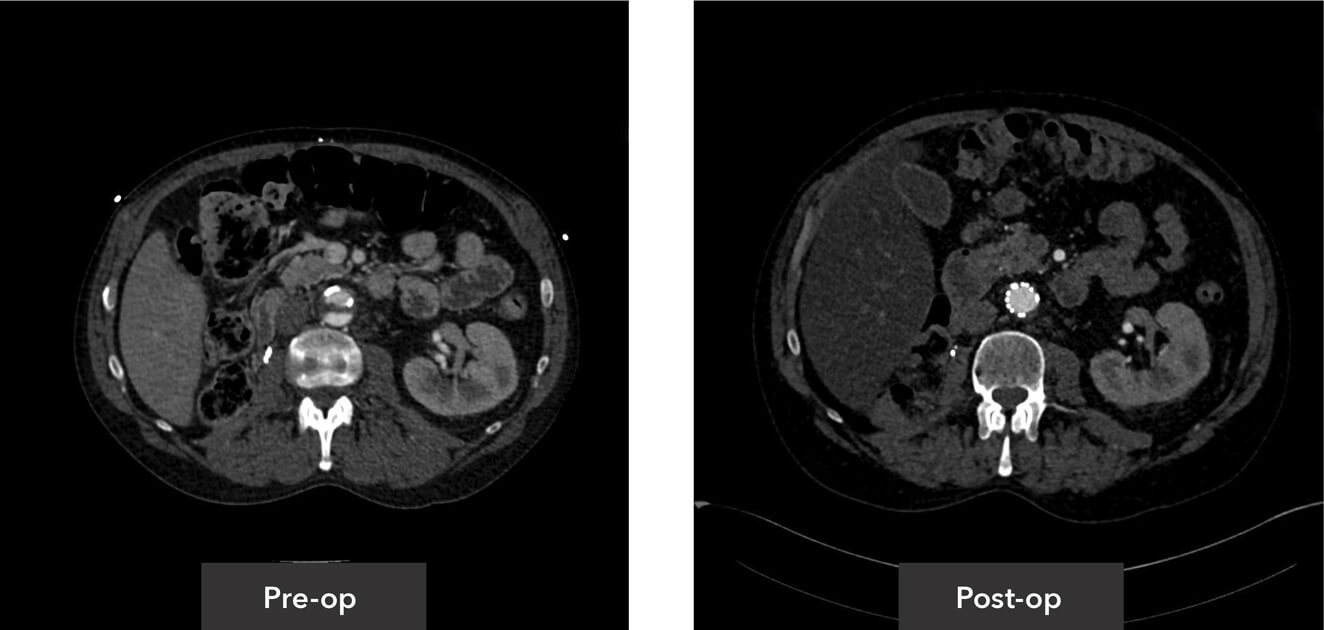

Abdominal aorta view pre-op/post-op axial view CT imaging